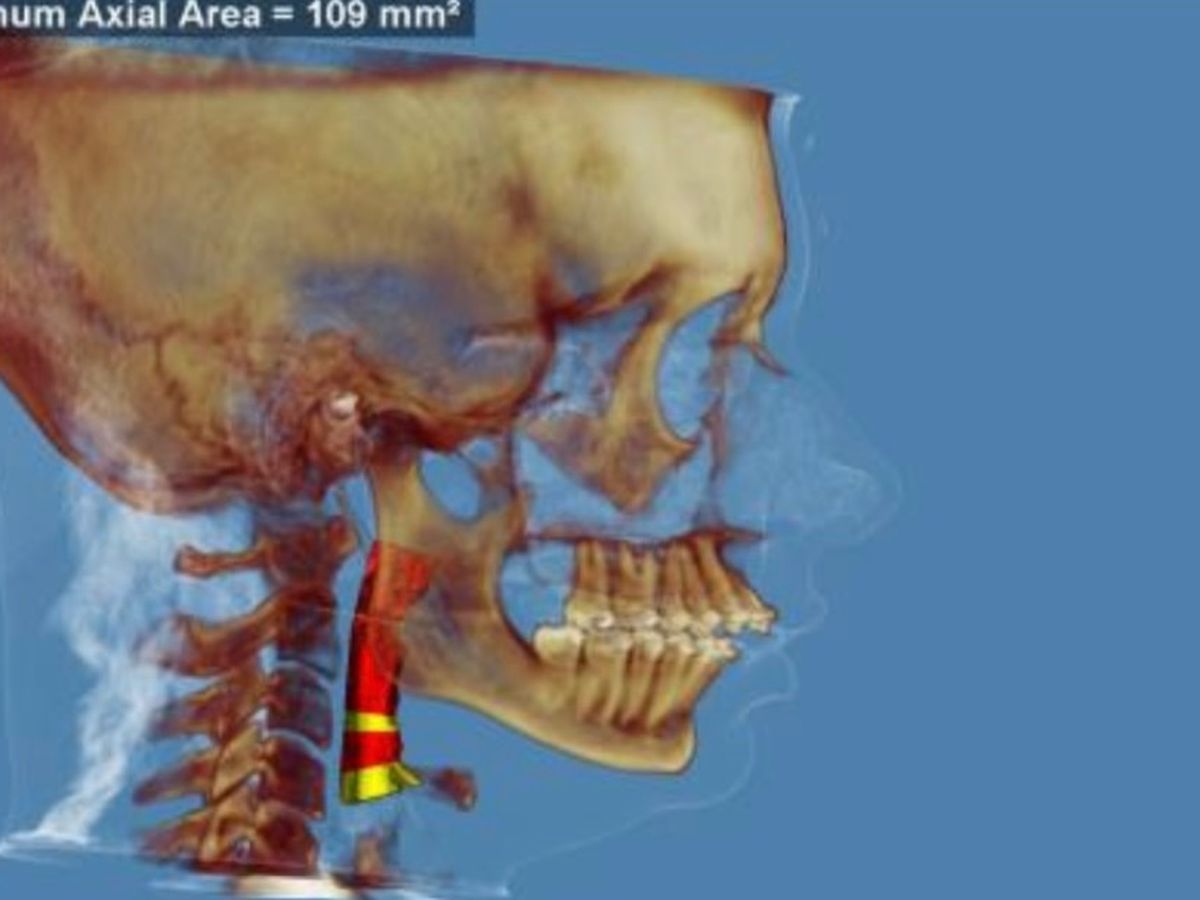

- My airway is too small, as shown in the header image. My risk of sleep apnea is high - and my dad who had the same jaw, died of sleep apnea. A small airway also worsens chronic pain I suffer due to EDS. Many people receive this surgery due to only small airway and without the additional bite issues I have. For me, both are why I need it.